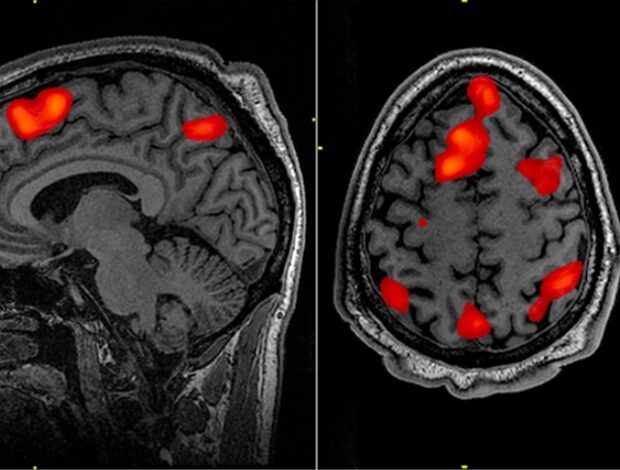

Nový výzkum mezi respondenty Světového obchodního centra (WTC) s chronickou posttraumatickou stresovou poruchou (PTSD) odhalil měřitelné fyzické změny ve struktuře jejich mozku, v souladu se změnami v rovnováze myelinizovaných a nemyelinizovaných neuronů (rychle a pomalu vodivé nervové buňky) napříč oběma hemisférami mozku. Tyto změny byly nejsilněji spojeny s opětovným prožíváním symptomů u jedinců s PTSD. Kortikální rozdíly nalezené v této sofistikované zobrazovací studii v Biologická psychiatrie: kognitivní neurověda a neurozobrazovánípublikoval Elsevier, mohou sloužit jako náhradní biomarkery pro narušené zdraví mozku u lidí trpících chronickou PTSD, stejně jako potenciálně informující o strategiích časného screeningu.

Tato studie používala neuroimaging šedo-bílý kontrast (GWC), což je technika založená na MRI, která má zlepšit studie neuronálního zdraví u traumatizovaných jedinců. GWC funguje jako proxy pro hustotu intrakortikální myelinizace a zkoumá zjevné rozostření na rozhraní bílé hmoty a šedé hmoty na základě rozdílů v intenzitě signálu. Zvýšení kontrastu představuje ostřejší hranici, svědčící o zdravém přechodu od šedé hmoty k bílé mozkové hmotě. Méně zřetelná hranice (nízká GWC) naznačuje abnormální koncentraci myelinu (tuková izolační vrstva), což ukazuje na narušení rychlosti zpracování a konzistence mozku.

Při vyhodnocování strukturálních snímků mozku u 99 respondentů WTC výzkumníci našli důkazy o rozsáhlých změnách v GWC v kortikální šedé hmotě napříč oběma hemisférami mozku u lidí s PTSD. Snížení GWC by mohlo znamenat, že v těchto oblastech je více obsahu myelinu, než je normální u pacientů s traumatem bez PTSD. Zjistili také, že GWC lze kombinovat s dalšími markery intrakortikálního zdraví, aby se zlepšila schopnost pomoci objektivně identifikovat WTC respondéry s PTSD.